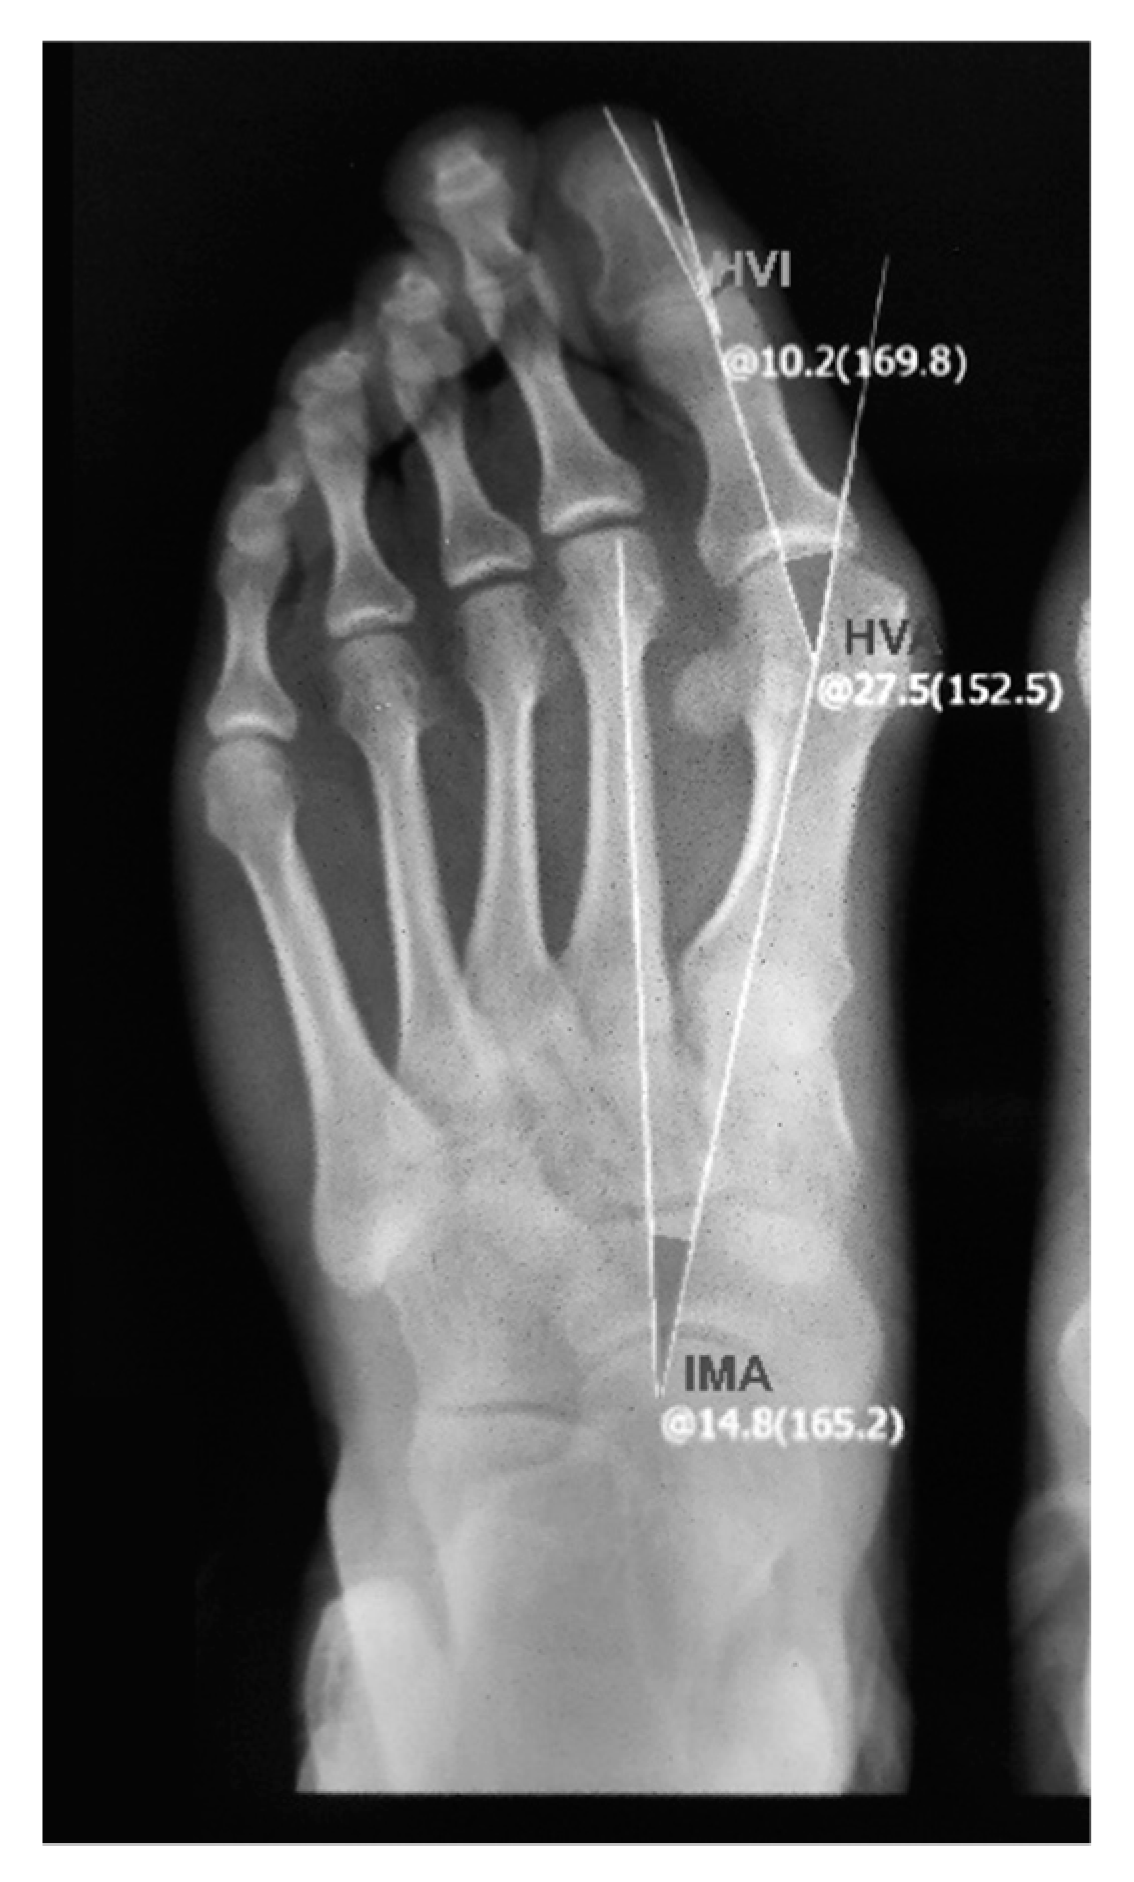

2.4. X-ray Measurement to Determine HVA

X-ray photographs can provide a detailed structure of the foot to examine the three important radiographic parameters: HVA, IMA and HVI (the hallux valgus interphalangeal angle), as shown in Figure 3. In the current research, X-ray photographs were captured by a radiographic scanner (Yuwell DR 60); then, a consultant defined the longitudinal axis of the foot and the dashed lines on the digital image, as shown in Figure 3. The HVA was obtained from the X-ray photographs using measurement software.

Figure 3.

Radiograph of HV foot with radiographic parameters (HVA, IMA and HIA) captured by a radiographic scanner (Yuwell DR 60).